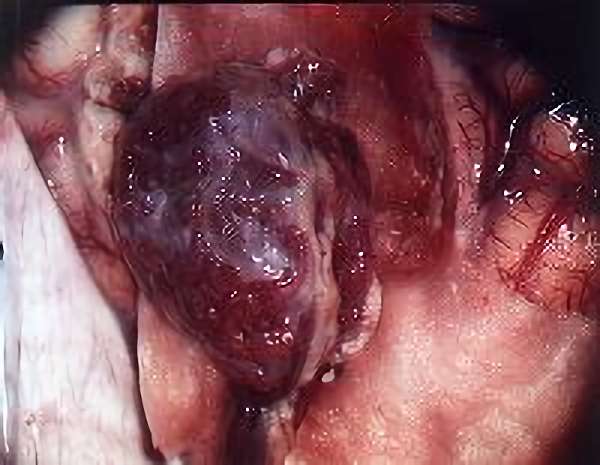

手術写真

手術中